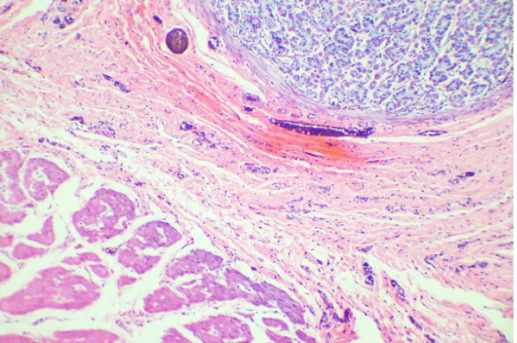

器官组织切片

![]() | ![]() | |

普通彩色相机采图结果 | 大恒图像相机色彩优化后 |

肠切片 | 肺切片 |